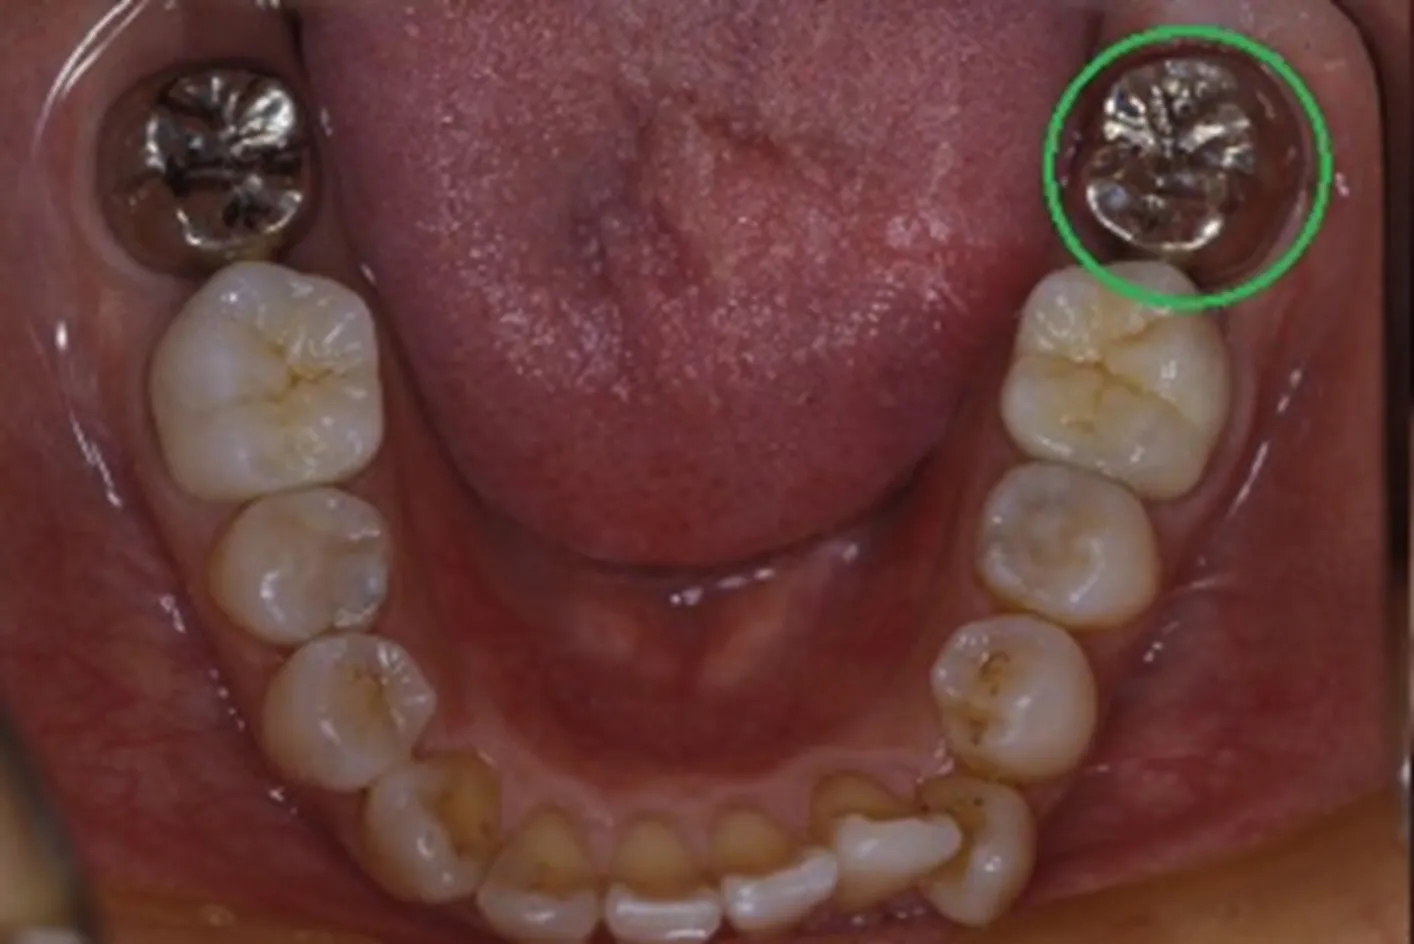

初診時

治療完了時

| 患者様のお悩み | 咀嚼障害(左下奥歯) |

| 治療法・使用素材 | 自家歯牙移植治療 |

| 患者様の年代 | 30代 |

| 治療開始年齢 | 30代 |

| 治療にかかった期間 | 6か月 |

| 性別 | 女性 |

| この治療のリスクについて | 移植歯が生着するかどうか |

| 治療にかかった費用 | 5万円 |